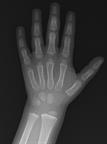

An X-ray showing the lower arm, wrist, and hand.

Las radiografías son imágenes del interior del cuerpo. Un equipo de radiografías produce estas imágenes mediante ondas de energía llamadas radiación. El médico podría usar radiografías para buscar ciertos problemas, como fracturas de huesos, problemas en las articulaciones, infecciones pulmonares y causas de dolor abdominal.